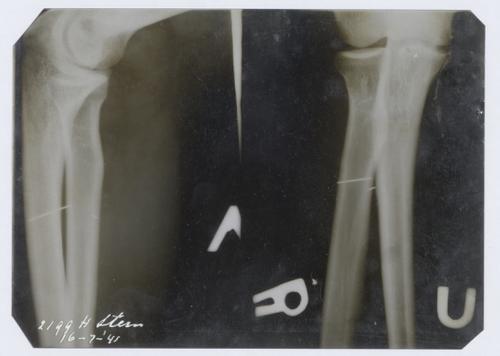

Enveloppe met röntgenfoto van Herta Stern, 1941

1941-07-16